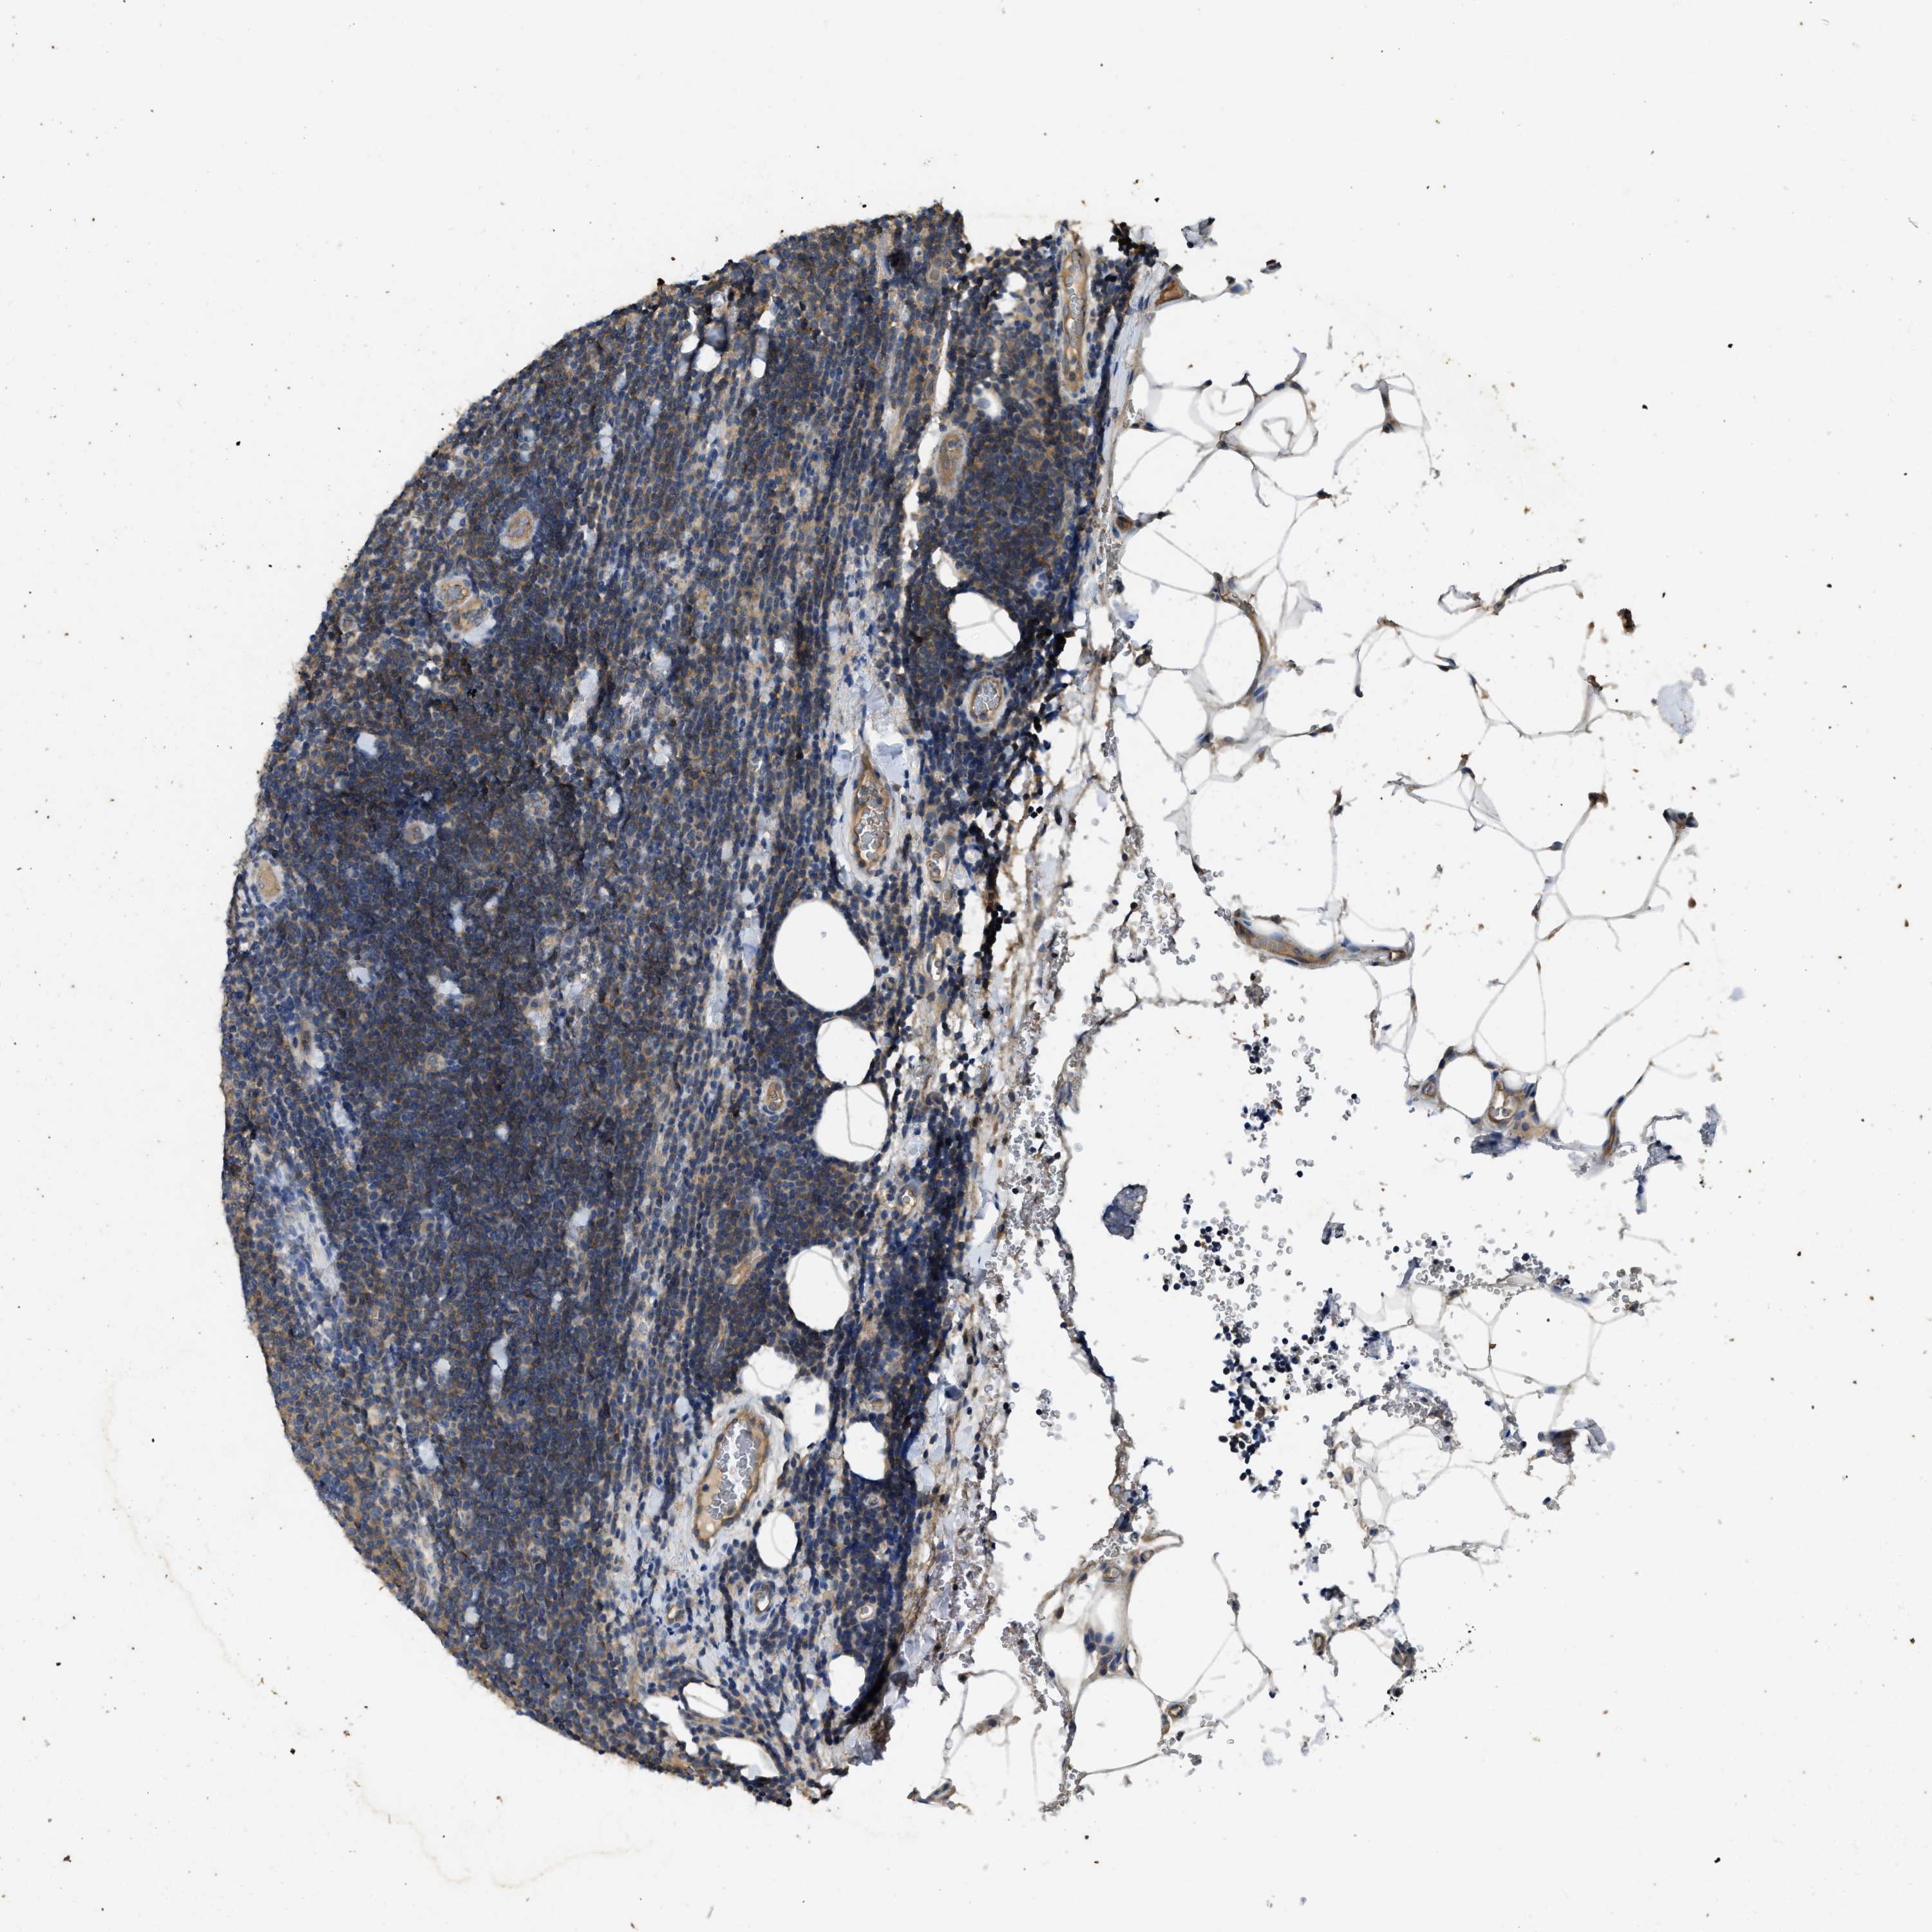

CANCER LYMPHOMA Show tissue menu

LYMPHOMA - Protein expressioni

A mouse-over function shows sample information and annotation data. Click on an image to view it in a full screen mode. Samples can be filtered based on level of antibody staining by selecting one or several of the following categories: high, medium, low and not detected. The assay and annotation is described here.

Antibody stainingi

Antibody staining in the annotated cell types in the current human tissue is reported as not detected, low, medium, or high, based on conventional immunohistochemistry profiling in selected tissues. This score is based on the combination of the staining intensity and fraction of stained cells.

Each image is clickable and will lead to virtual microscopy that enables deeper exploration of all samples and also displays staining intensity scores, fraction scores and subcellular localization as well as patient and tissue information for each sample.

Antibody HPA012778

Antibody CAB018581

Staining

High

Medium

Low

Not detected

Intensity

Strong

Moderate

Weak

Negative

Quantity

>75%

75%-25%

<25%

None

Location

Nuclear

Cytoplasmic/membranous

Cytoplasmic/membranous,nuclear

Hodgkin's disease, NOS

Malignant lymphoma, non-Hodgkin's type, High grade

Malignant lymphoma, non-Hodgkin's type, Low grade